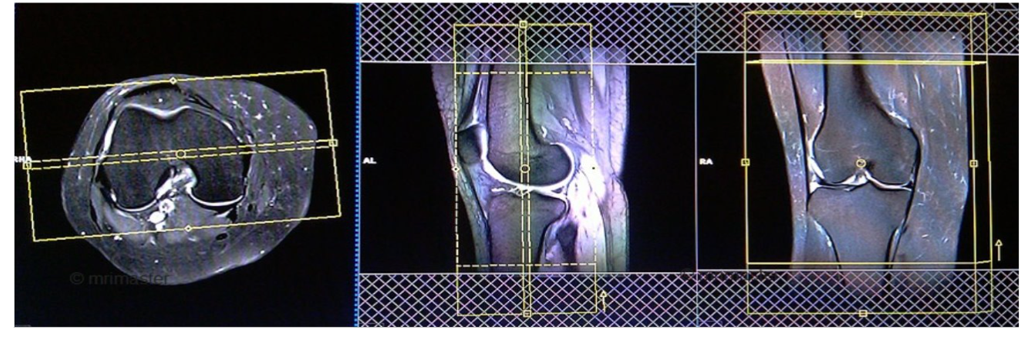

AXIAL

CORONAL

SAGITTAL